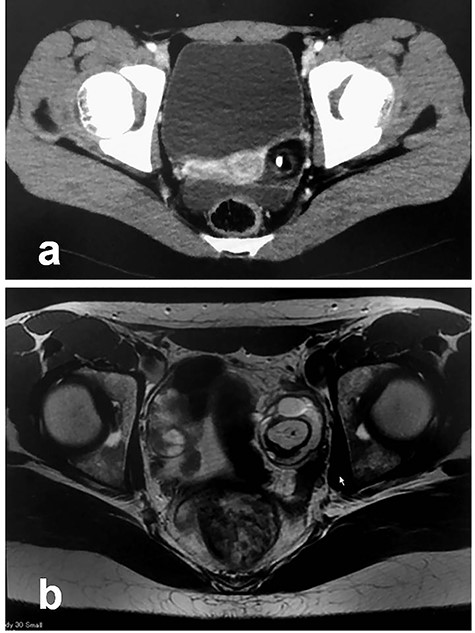

Patient 1: In a 12-year-old girl with abdominal pain, enhanced computed tomography (CT) showed a swollen appendix and a left ovarian mass; she was diagnosed with appendicitis (Fig. 1a). After laparoscopic appendectomy, she underwent magnetic resonance imaging (MRI), which revealed an ovarian MCT (38 cm × 30 cm; Fig. 1b). She underwent a second procedure, laparoscopy-assisted extracorporeal cystectomy (a hybrid, minimally invasive approach), during which the tumor was placed in a specimen retrieval bag and exteriorized through a suprapubic incision. The tumor was then excised, and the ovary returned to the pelvis. There was no content spillage (Fig. 2). The excised margins of the tumor were continuously oversewn using absorbable suture. Pathologic examination confirmed the diagnosis of MCT. The patient has been doing well without evidence of recurrence. She subsequently established a regular menstrual cycle.